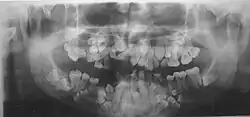

- Нарушения формирования корней, задержка в прорезывании молочных и постоянных зубов. Могут до 25-30-летнего возраста не меняться молочные зубы. Часто встречаются сверхкомплектные зубы.

Диагностика ключично-черепного дизостоза основана на клинических симптомах и рентгенологических исследованиях, которые включают изображения черепа, грудной клетки, таза и рук. Главный рентгенологический симптом — дефекты ключиц. Обычно отсутствует наружный (акромиальный) конец ключицы, в то время как внутренний (грудинный) конец присутствует. Но иногда ключица состоит из двух фрагментов. Полное отсутствие ключицы встречается редко.

Заболевание в целом неизлечимо. Но чаще всего необходимо лечение проблем зубов, как наиболее значимых, причем начинать надо с детского возраста:

- Удаление молочных зубов.

- Удаление сверхкомплектных зубов.

- Ортодонтическое лечение.